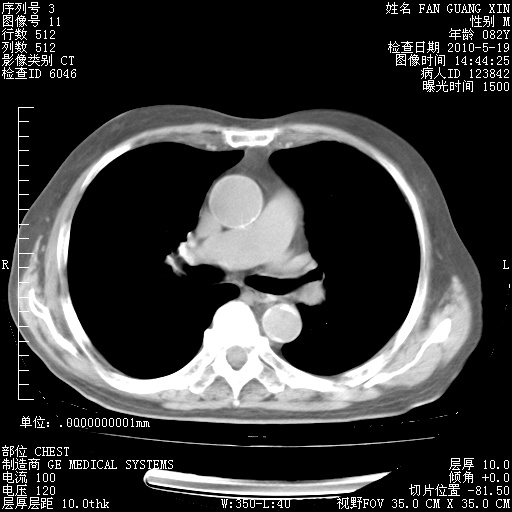

复查肺部CT,明显好转。为什么发热呢?

治疗3周后的肺部CT

治疗3周后的肺部CT纵隔窗